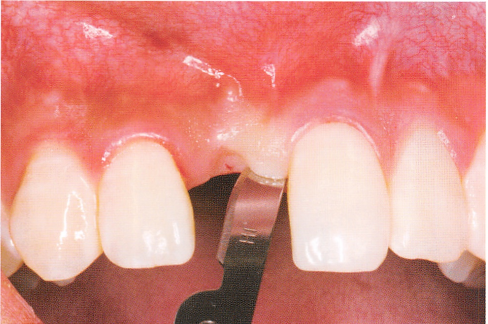

2.注意美学效果遵循微创原则,避免粗暴操作,缩小剥离范围,减少术后搬痕产生。切口设计尽量避开牙龈乳头,以免形成瘢痕降低牙龈乳头高度,从而影响美观。二期手术切开时尽量沿原有的瘢痕切开,避免产生新的瘢痕。但在后牙种植区为了避免操作时视野不清晰,可适当增大切口范围以充分暴露术区。